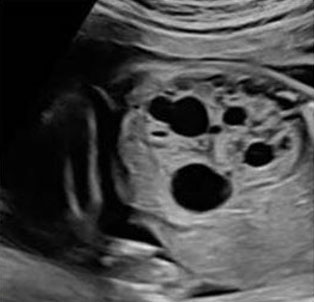

Imaging

The best diagnostic clue for MCDK is multiple, different sized cysts seen in the renal fossa. Multicystic dysplastic kidney presentation can vary greatly from the size of the kidney, laterality, and associated anomalies (Figure 12). More often non-communicating cysts are found only in the left kidney with an increased renal size and loss of reniform shape [34]. Bilateral MCDK is associated with poor prognosis. In 40% of cases a non-MCDK anomaly is found in the contralateral kidney [11].

Diagnostic checklist

In MCDK, it is important to evaluate the function of the contralateral kidney with follow-up ultrasounds and amniotic fluid measurements. It is also important to determine that cysts do not communicate. There may be a presentation of “hydronephrotic type” of MCDK that shows large cysts surrounded by smaller cysts [9]. If a cystic mass in the pelvis is visualized, consider MCDK in a pelvic kidney (Figure 12).

Figure 12: Ultrasound image showing a MCKD anomaly, multiple non-communicating cysts are seen within the kidney, separated by echogenic renal parenchyma suggestive of dysplasia [26]. Radiological images were obtained from open-access article distributed under the terms of the Creative Commons Attribution License (CC BY) [26].